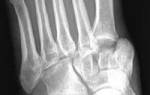

Вывихи пальцев кисти

В межфаланговых суставах и в суставе между пястной костью и основной фалангой пальца возможны вывихи. Чаще всего наблюдается вывих первого пальца. Травма возникает при чрезмерном разгибании, реже — сгибании. Вывих сопровождается деформацией, отеком и резкой болью. Движения в травмированном суставе невозможны. Вправление вывиха осуществляется путем тяги за палец. Если вправление невозможно, это может быть связано с ущемлением мягких тканей, и в таком случае требуется оперативное вмешательство.